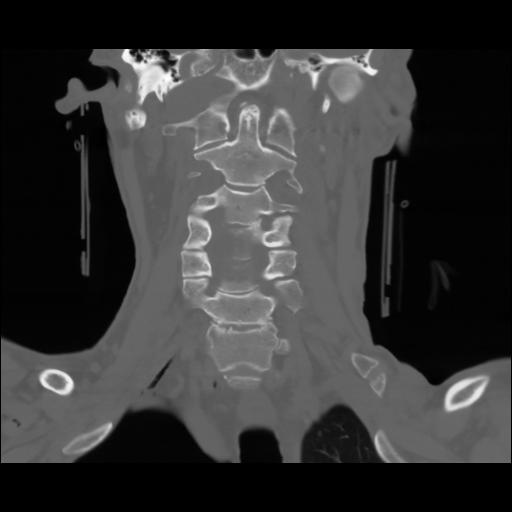

13 P.BLANDAS,,Coronal,2.000,P.BLANDAS,Coronal,